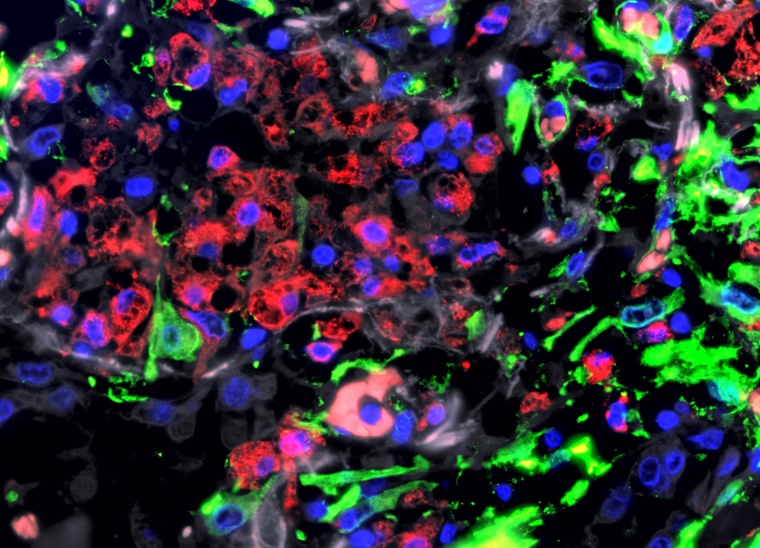

Das Team konnte so zeigen, dass sich in der Lunge von COVID-19-Betroffenen, die ein Lungenversagen entwickeln, vor allem Makrophagen in großen Mengen ansammeln. Diese Fresszellen beseitigen z.B. eingedrungene Erreger oder Zellabfall, sind aber auch an der Wundheilung und Reparatur von Gewebe beteiligt. „Überraschenderweise zeigten die Makrophagen bei schwerem COVID-19 ähnliche Eigenschaften wie bei einer chronischen Form der Lungenvernarbung, der idiopathischen Fibrose“, betont Dr. Saliba. Bei dieser unheilbaren Erkrankung vernarbt die Lunge unaufhaltsam bis zum Verlust der Organfunktion. Die Ursache ist unbekannt, unter allen Formen der Lungenfibrose hat sie die schlechteste Prognose. „Die Makrophagen treten bei schwerem COVID-19 mit bestimmten Zellen des Bindegewebes in Kontakt, die für die Bildung von Narbengewebe verantwortlich sind. Diese Zellen vermehren sich stark und produzieren große Mengen Kollagen“, ergänzt der Experte der Einzelzellforschung.

In der Zellkultur entdeckten die Wissenschaftler, dass SARS-CoV-2 selbst die Fresszellen so beeinflusst, dass sie den Fibroseprozess möglicherweise befeuern. Dazu isolierten sie Fresszell-Vorläufer aus dem Blut gesunder Menschen und stimulierten sie mit dem Virus. Wie eine Analyse von etwa 7.000 Proteinen zeigte, produzierten die Immunzellen daraufhin verstärkt Botenstoffe, die Vernarbungsprozesse einleiten, ganz ähnlich wie bei einer idiopathischen Lungenfibrose. „SARS-CoV-2 ist also zumindest ein möglicher Auslöser für die fehlgeleitete Reaktion der Fresszellen“, erklärt Prof. Dr. Matthias Selbach. Der Proteomik-Experte hat die Studie am Max-Delbrück-Centrums für Molekulare Medizin in der Helmholtz-Gemeinschaft (MDC) geleitet. „Das Virus vermehrt sich dabei anscheinend nicht in den Immunzellen, sondern programmiert sie um. Diesen Effekt konnten wir interessanterweise nicht beobachten, wenn wir die Makrophagen mit einem Grippevirus stimulierten. Das Influenza-Virus vermehrte sich in den Immunzellen stark. Es brachte sie aber nicht dazu, Vernarbungsprozesse zu fördern.“